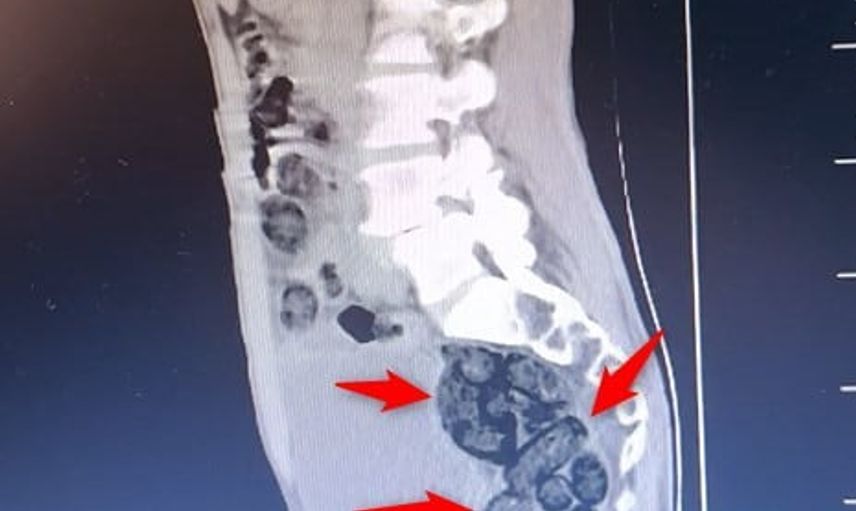

Aramada durumundan şüphelenilen yabancı uyruklu bir yolcu üzerinde yapılan incelemede, şahsın midesinde 64 parça halinde toplam 472 gram metamfetamin bulunduğu tespit edildi.

Bulunan uyuşturucu, sağlık ekiplerince şahsın midesinden çıkartıldı. Emniyetteki işlemlerinin ardından adliyeye sevk edilen şahıs, çıkarıldığı mahkemece tutuklanarak cezaevine gönderildi.